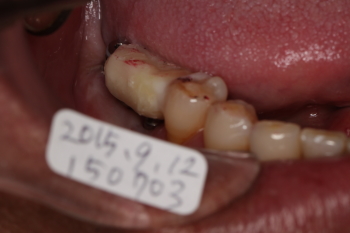

| テック(仮歯)を装着した状態です。 ミラーを使って、舌側から見た写真です。 上記の写真の裏側です。 |